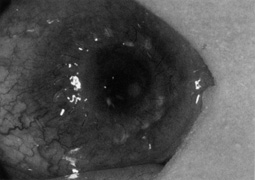

Wound healing is more rapid in children than it is in adults. As the wound heals it contracts, causing suture loosening. Loose sutures cause irritation and induce vascularization, mucus accumulation, rejection, and microbial infection (Fig. 9). Therefore, loose sutures should be removed immediately. Timing of routine suture removal depends on the patient's age and the degree of vascularization. Typically, suture removal is performed 4 to 6 weeks postoperatively in children younger than 1 year of age, 3 to 4 months postoperatively in young children, and 4 to 6 months postoperatively in older children.

Fig. 9. Loosened continuous suture with injection and mucus accumulation.